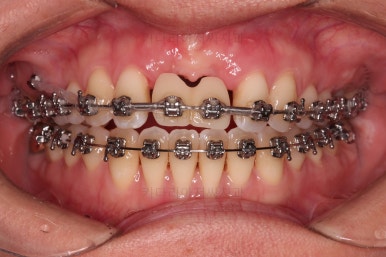

3. 치료과정

개방교합을 닫는 전략은 앞니를 약간 끌어내리고, 어금니를 앞니 위치로 약간 올려서 균형을 맞추는 건데요.

장치 부착은 윗니 어금니부터 했습니다.

미니스크류를 다양하게 활용하여 어금니 높이를 조절합니다.

여전히 앞니는 내버려둔 채로, 윗니는 어금니쪽만 진행하며 아랫니도 장치를 부착했습니다.

난이도가 매우 높은 치료인만큼 미니스크류의 구성과 장치 구성도 매우 복잡했는데요.

윗니 어금니를 뒤로 밀면서 앵글씨 2급 부정교합을 개선해 주고, 높낮이를 조절하면서 개방교합을 개선해 줍니다.